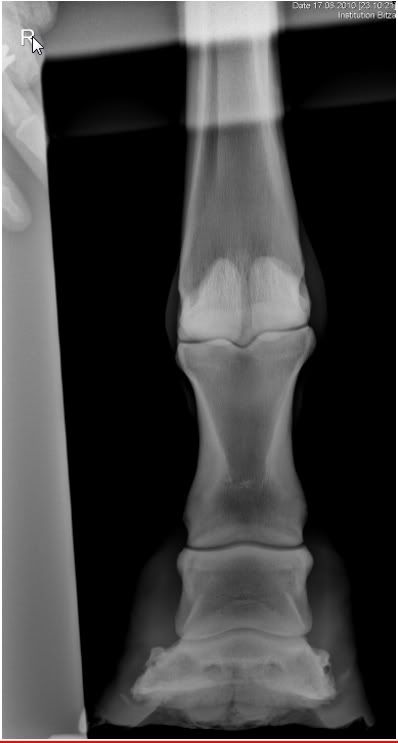

Потом таки доктора привезли! Забрала коня из денника, привязала, и начала мучить доктора вопросами. Показала рентген с нашим кривым суставом. Штрассер сказала, что конкретно кривой постав доставлять особого беспокойства не может и при наличии движения 24 часа в сутки, при нормальных копытах за пару лет может даже и исправиться. Но чтобы исправить постав, передние копыта надо расчищать чаще - раз в неделю. Ну, что ж, придется мне учиться, не отверчусь :mrgreen: